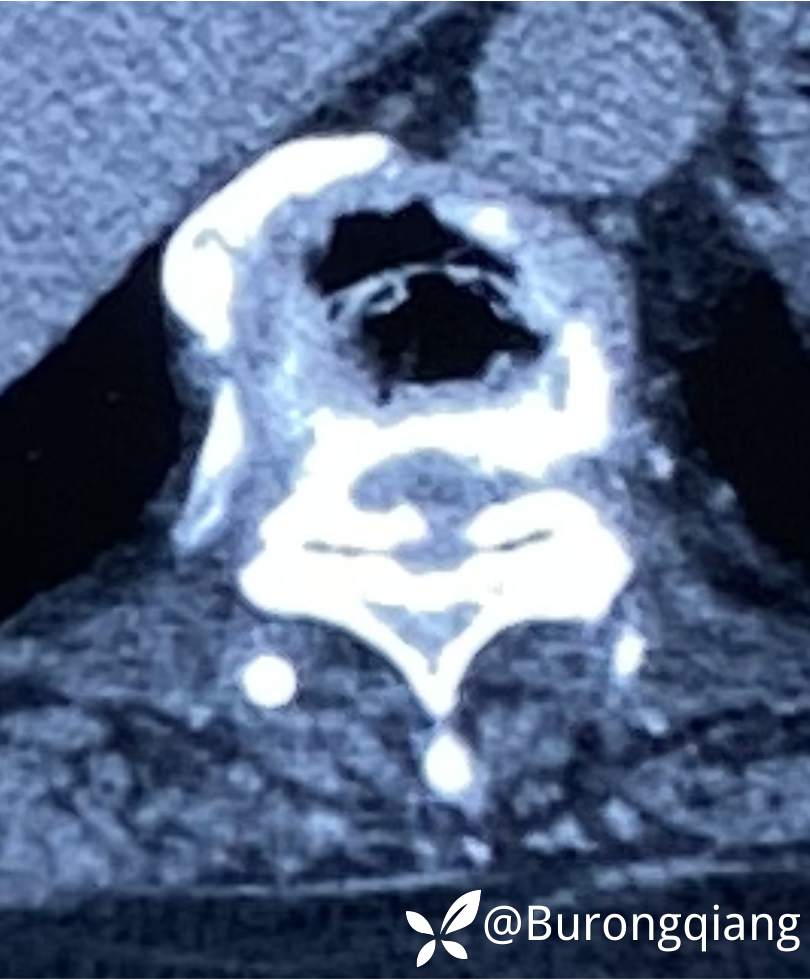

临床诊断:胸椎管狭窄

治疗经过:给予脊柱内镜下椎管扩大减压手术治疗。